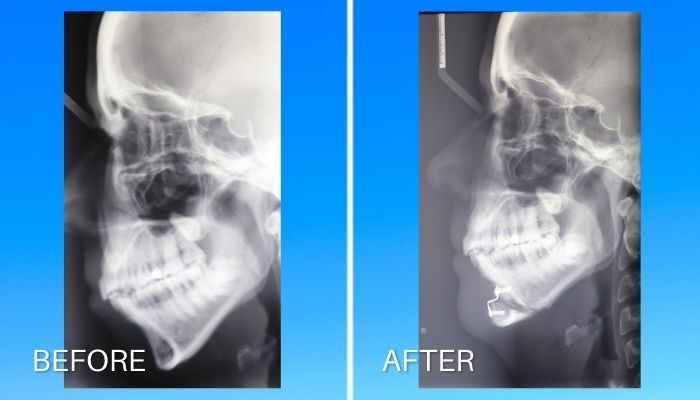

Example of such genioplasty in the case of a downgrown jaw

Dr John McHugh

Example of such genioplasty in the case of a downgrown jaw

Dr John McHugh